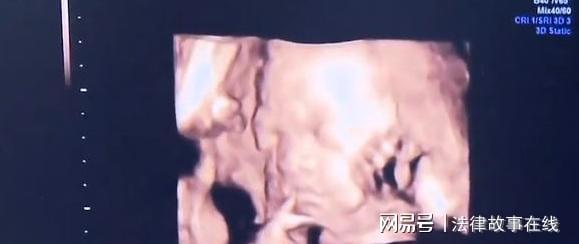

为了让妻子接受治疗,叶富不仅向妻子隐瞒了要花10万做化疗,还隐瞒了可能会对胎儿产生的影响。做完第一次化疗后,妻子感觉到胎动得很厉害,有些不正常。叶富吓得赶紧用手机上网搜资料,想查看到底会不会影响胎儿发育?不料,却被细心的张莹发现了。她一下抢过丈夫的手机,哭着追问他,为什么要瞒着自己用化疗药物?她宁可不活,也要保孩子周全。叶富只能安慰她,孩子很坚强,不会有事的。一星期后,张莹和肚子中的宝宝,很幸运地存活了下来。不放心的夫妻俩又来到B超室,检查孩子情况。那么,能保住这个孩子吗?正当叶富和妻子沉浸在喜悦中时,医生的话当头给他们泼了一瓢冷水,做过化疗后,胎儿都会受到影响。不仅如此,张莹还必须做第二次化疗,要想彻底治好病,以后还得做骨髄移植。因此,医生建议张莹立刻做引产手术。